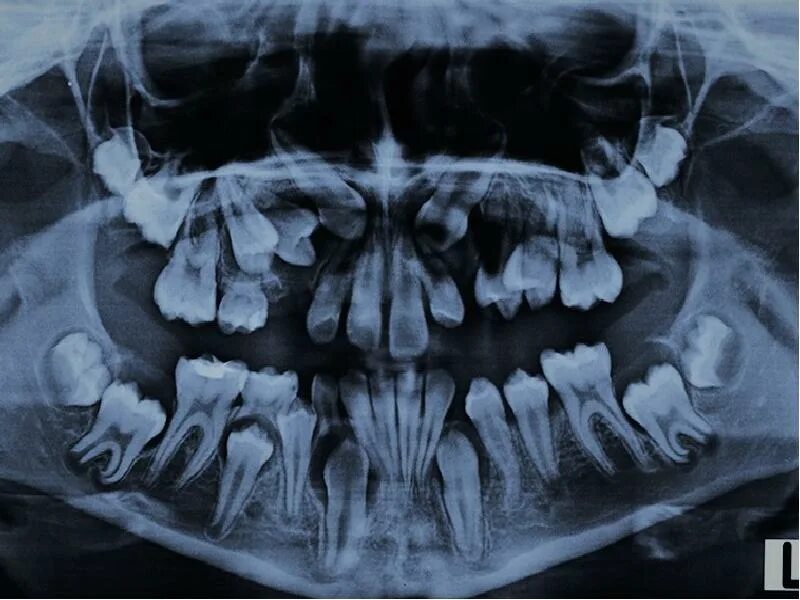

Зуб дистопирован